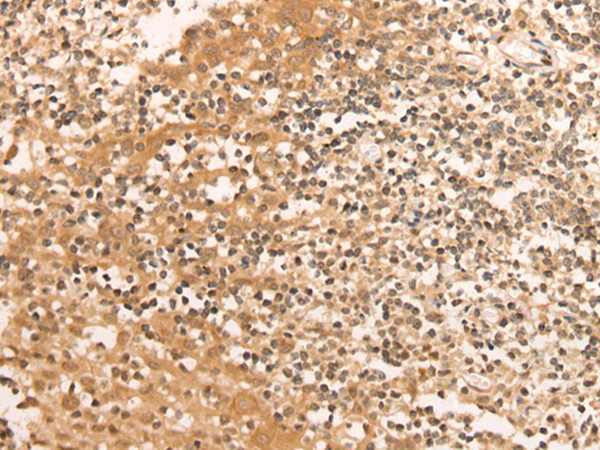

分类: 科研抗体货号: P02429别名: C1orf93; FAM213B应用: WB,IHC反应种属: Human, Mouse, Rat